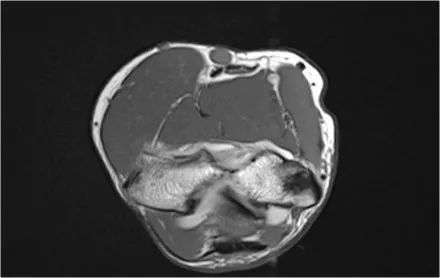

需要确保以标准化的方式正确地获得成像平面,在轴向定位器上使用肱骨髁的轴来规划冠状扫描,矢状图像垂直于冠状扫描进行扫描。

通过这种方式,获得良好的图像,这些是我们所习惯正常的解剖结构

当你研究肘部的解剖结构时,最好使用由内而外的方法。首先研究骨骼,然后继续韧带和肌腱,然后是周围的结构。